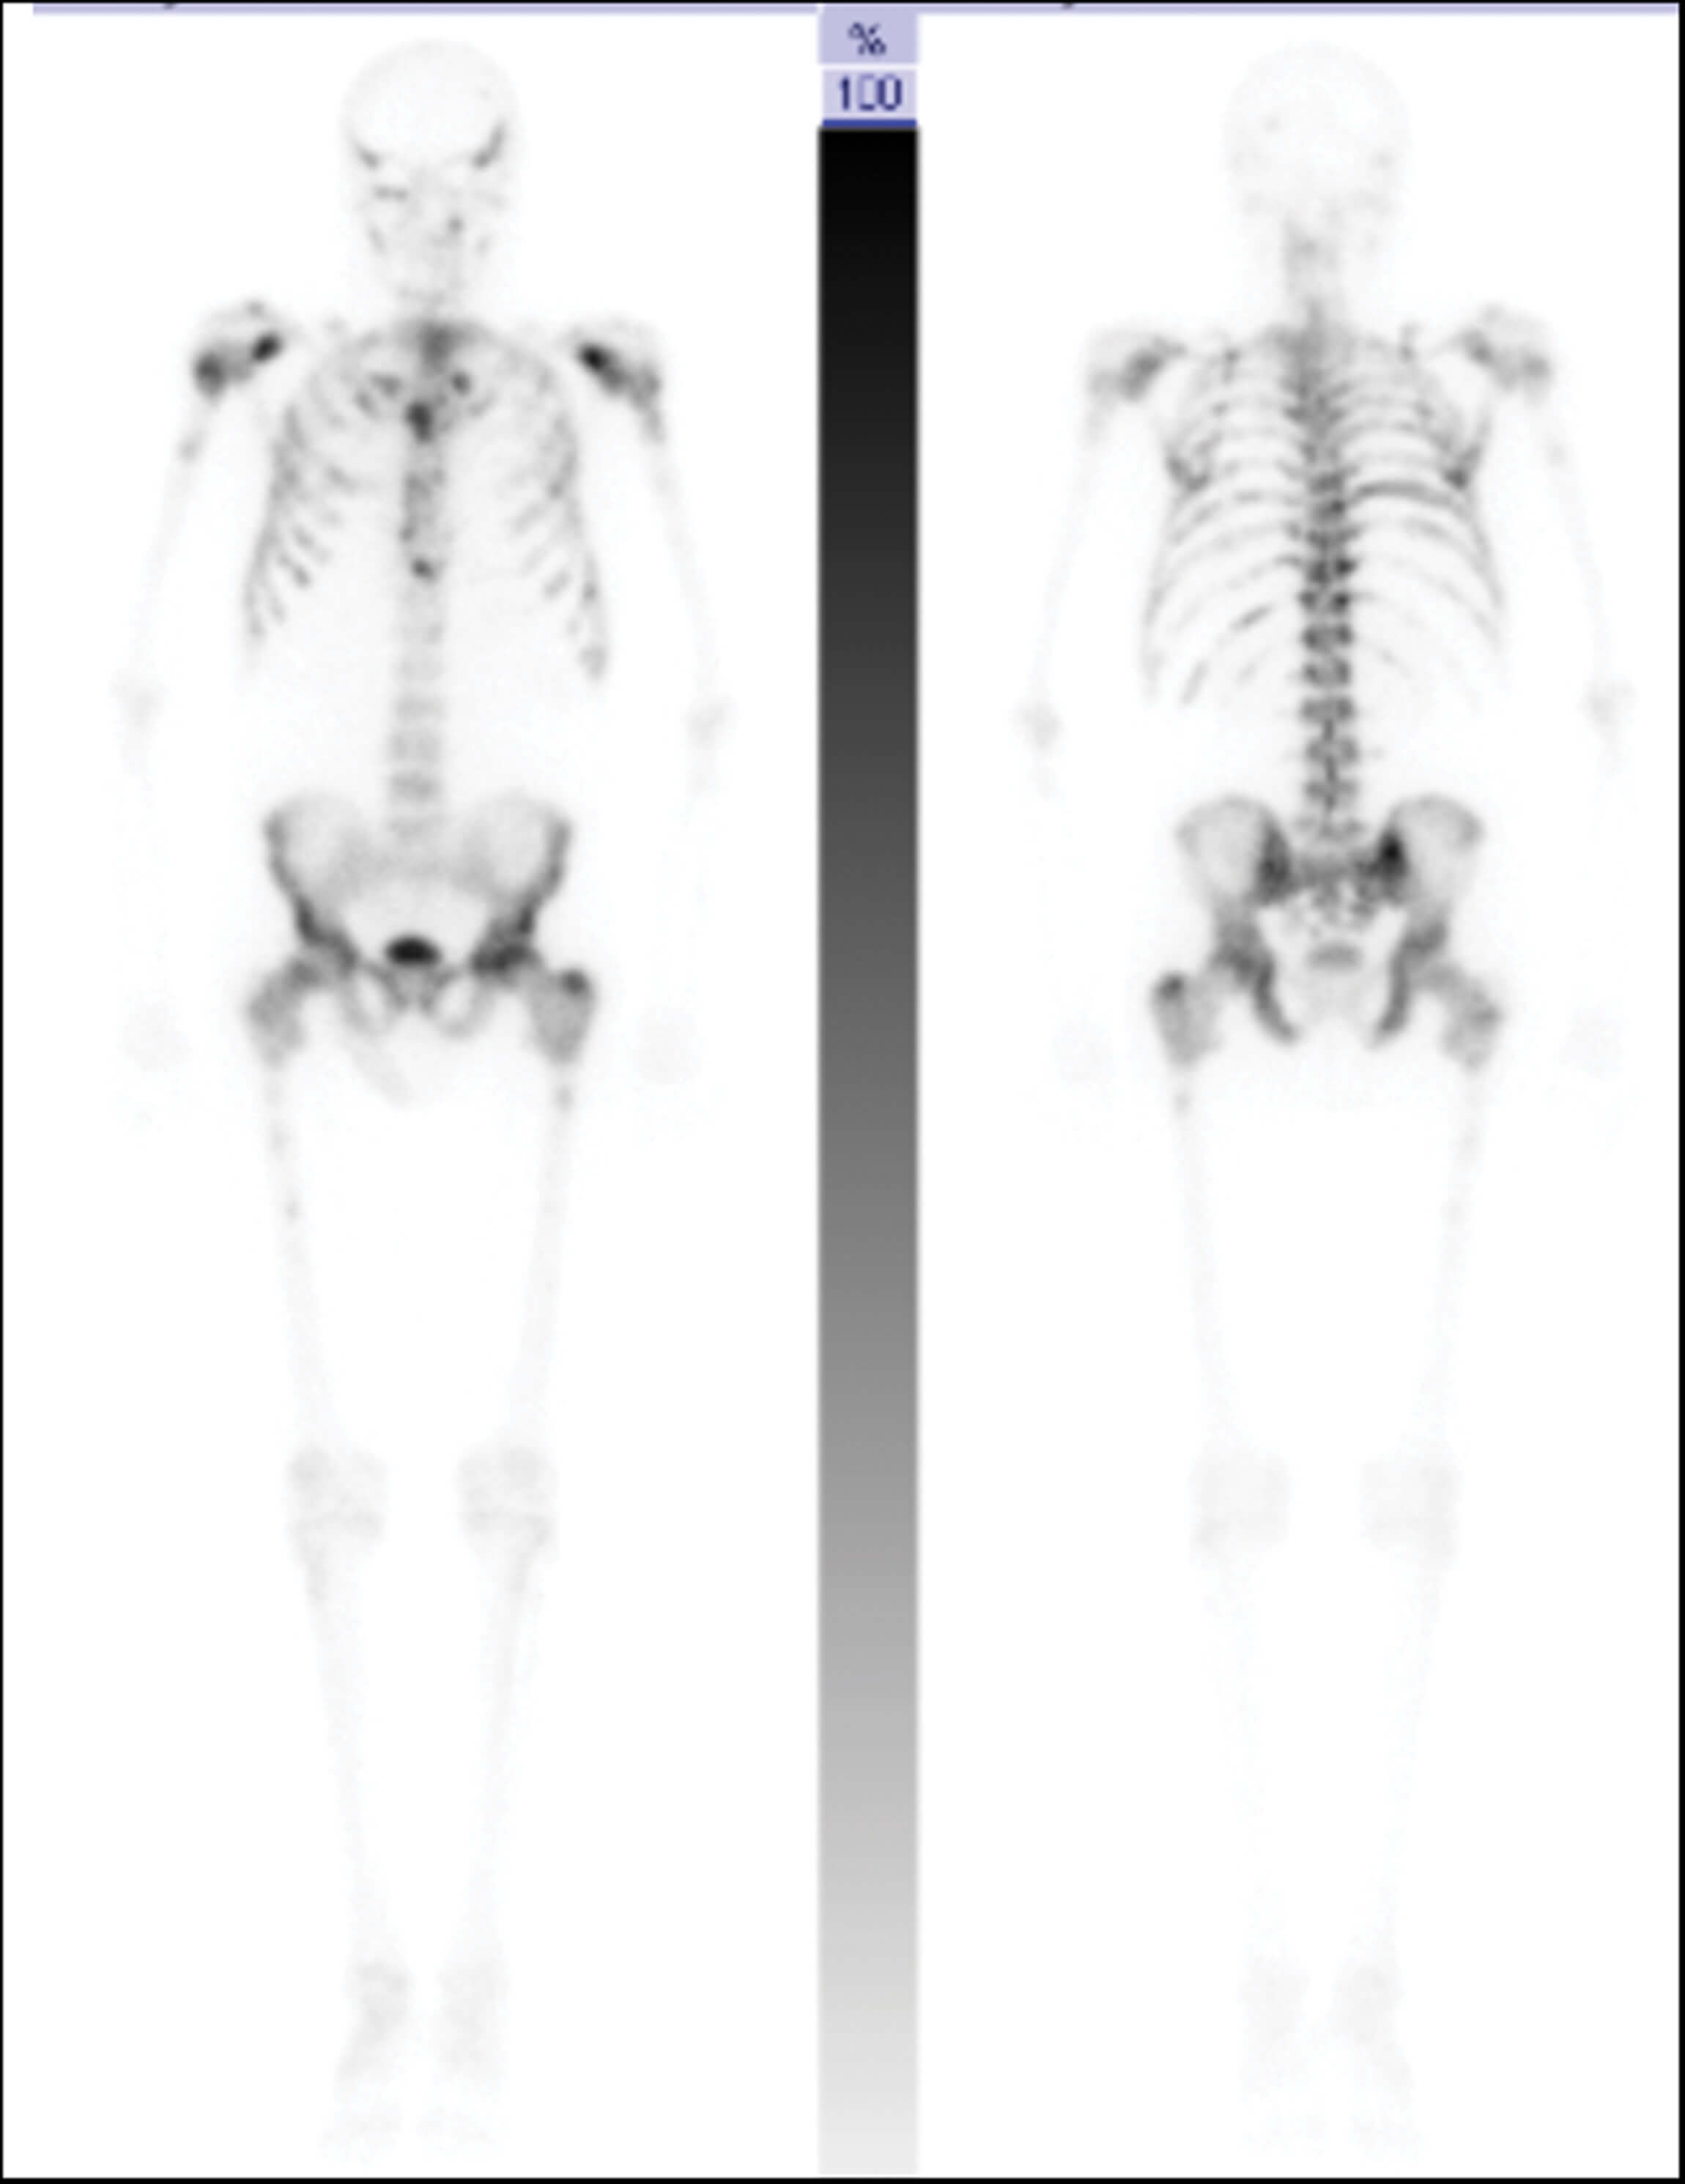

- he patient undergoes further imaging as part of staging his disease. What type of scan is shown in Figure 1 and what does it show? How sensitive and specific is this modality?

2. This is an isotope whole body bone scan which uses Technetium-99 (99mTc) tracer to demonstrate high bone activity such as in bone metastases. For the patient in this case, there are several areas of increased tracer uptake throughout the skeleton corresponding to extensive bone metastases. There is no tracer uptake in the kidneys, a finding known as ‘Super Scan’, due to the extensive osteoblastic metastases causing diminished renal and background soft tissue uptake. Bone scans are indicated in prostate cancer for patients who are CPG3 and above, any concern for bony metastases and patients on watchful waiting with a high risk of bony metastases [2]. The reported sensitivity is 79% and specificity is 82% [3].